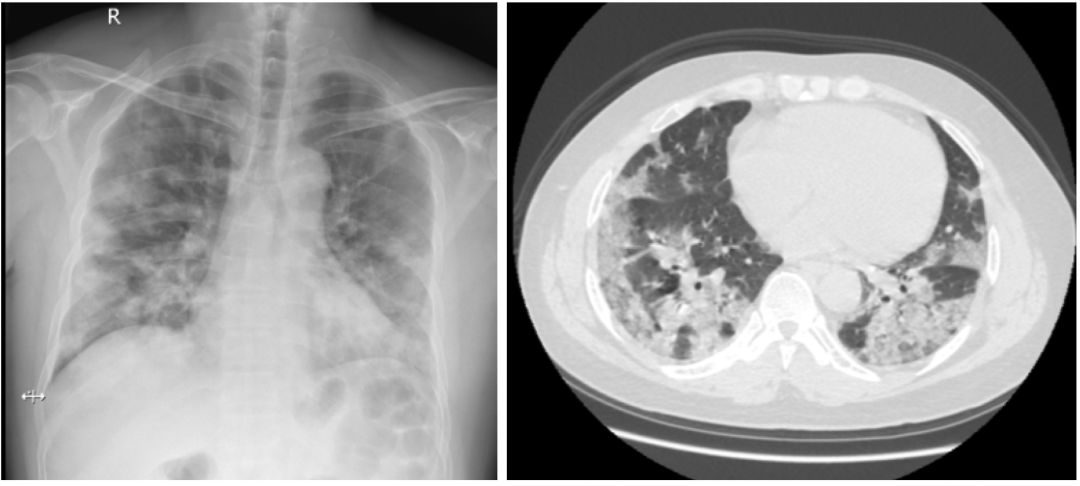

由细菌感染导致的流感患者的肺炎,称为流感病毒相关性细菌肺炎,它比单纯性流感病毒肺炎更为常见。临床表现为咳脓性痰,外周血白细胞明显增多,以中性粒细胞为主。胸部影像基础病变为浸润影和实变影【图3、图4】,可表现为支气管肺炎或大叶性肺炎。流感病毒相关性细菌肺炎还可分为两种类型:「细菌同时感染型」和「继发细菌感染型」。前者是指当流感症状减轻后2~7天,在受损的肺或支气管上继发细菌感染;后者是指在流感病毒感染的同时,即有细菌感染。后者的临床表现一般比前者更为严重。

图3                                                                                                                图4